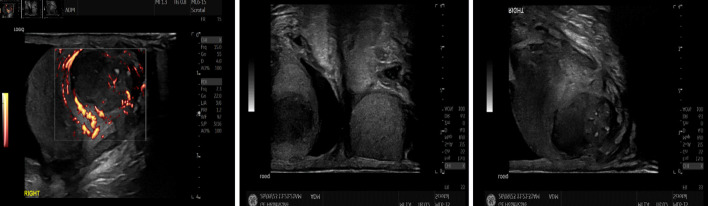

This case report describes an 85-year-old patient who presented with painless, unilateral right testicular swelling of 2 months' duration. This raised the possibility of testicular cancer, especially given his recent treatment for bladder cancer, which included adjuvant intravesical bacillus Calmette-Guerin (BCG) therapy. This poses a diagnostic dilemma regarding tuberculosis (TB) of the testis, BCG complications or a true testicular malignancy. Biochemical markers and a computed tomography (CT) scan showed no evidence of malignancy or disseminated TB. A TB-ELISpot test was negative. An ultrasound of the testis revealed a hypoechoic soft tissue lesion measuring approximately 24 × 19 mm, with internal vascularity and calcifications, causing a bulge in the testicular capsule with probable extracapsular extension. Based on the clinical suspicion of a testicular tumor, a right inguinal orchidectomy was performed. Histopathologic examination revealed isolated tuberculous orchitis with focal epididymal involvement; the spermatic cord was not involved. Polymerase chain reaction (PCR) testing on the histological sample confirmed the presence of Mycobacterium bovis DNA. As a radical right orchidectomy had been performed, no abnormal tissue remained. Additionally, the CT scan showed no evidence of TB dissemination, and the patient was asymptomatic, so he was being closely monitored in the infectious disease clinic. Importantly, a urine culture became positive for TB, and he was started on antituberculosis medication. BCG-induced granulomatous epididymo-orchitis may rarely occur as a late complication following intravesical BCG therapy for superficial bladder cancer. In this case report, we attempted to understand the pathophysiology, diagnostic challenges, patient implications, and potential future research directions.